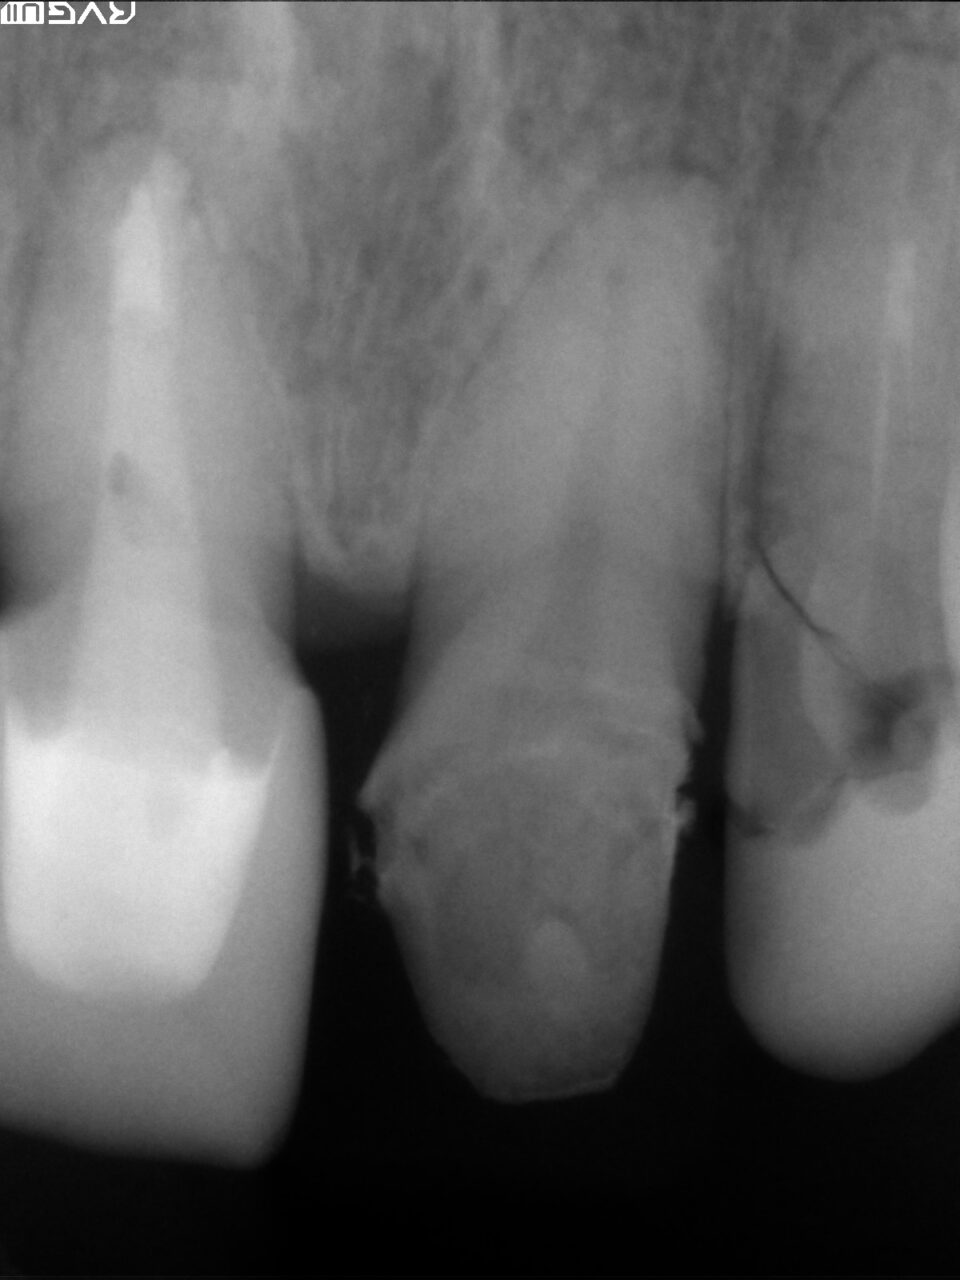

レントゲン像から外傷による歯髄炎を起こして抜髄処置を行ないました。(術前の口腔内写真、レントゲン)

術前レントゲン写真、隣の歯も外傷による歯根破折がレントゲンから確認できます。